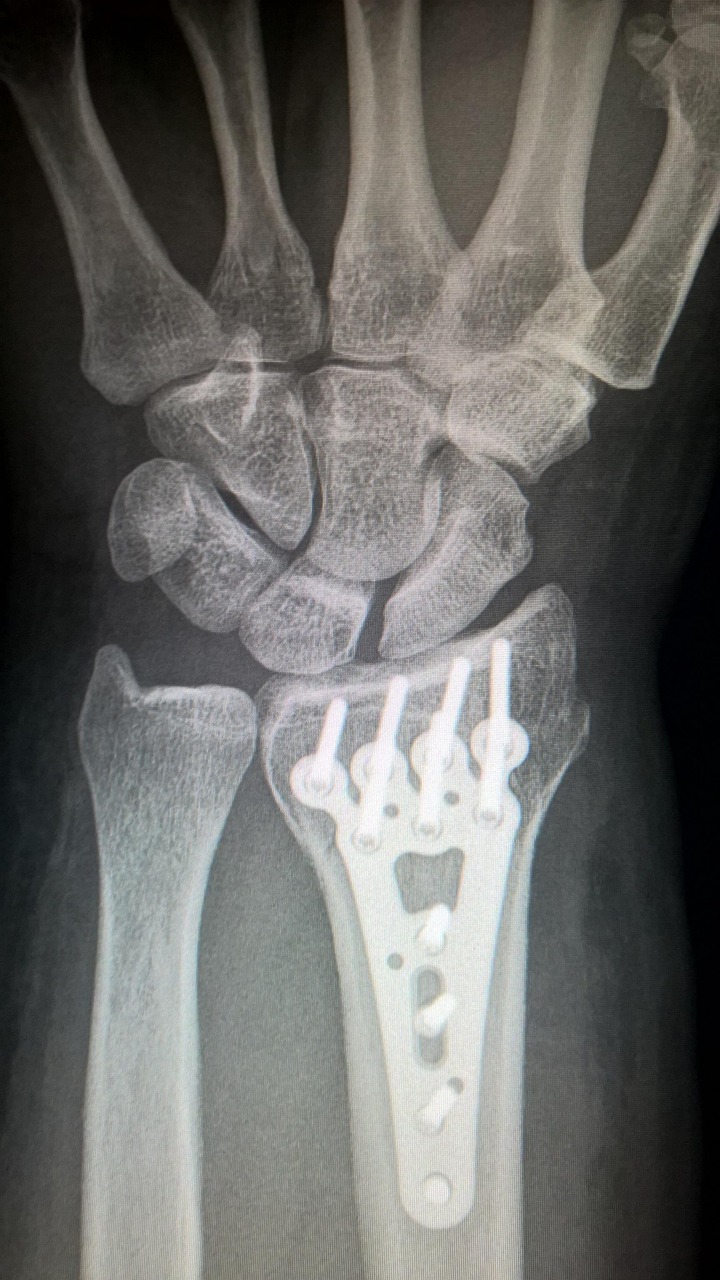

Ein Besuch beim Orthopäden sollte in Betracht gezogen werden, wenn Rückenschmerzen länger als einige Tage anhalten oder sich verschlimmern. Insbesondere wenn die Schmerzen mit weiteren Symptomen wie Taubheitsgefühlen, Schwäche in den Beinen oder Problemen beim Gehen einhergehen, ist es ratsam, einen Facharzt aufzusuchen. Diese Symptome können auf ernstere Erkrankungen hinweisen, die eine sofortige medizinische Intervention erfordern. Auch wenn die Schmerzen nach einem Unfall oder einer Verletzung auftreten, sollte umgehend ein Orthopäde konsultiert werden. Darüber hinaus ist es wichtig, einen Spezialisten aufzusuchen, wenn die Rückenschmerzen die täglichen Aktivitäten beeinträchtigen oder Schlafstörungen verursachen. Ein Orthopäde kann durch gezielte Untersuchungen und bildgebende Verfahren wie Röntgen oder MRT die genaue Ursache der Beschwerden feststellen und eine geeignete Therapie vorschlagen. Je früher eine Diagnose gestellt wird, desto besser sind die Chancen auf eine erfolgreiche Behandlung.